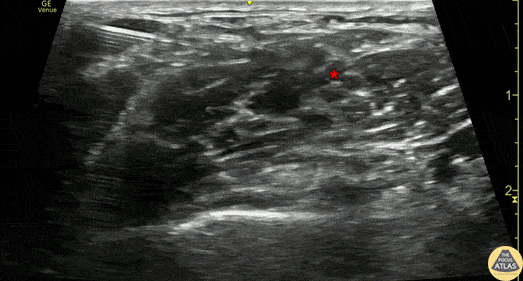

30s M with past medical history of recurrent shoulder dislocations who had failed prior surgery presented with anterior shoulder dislocation. An interscalene nerve block was performed for analgesia to facilitate reduction. After confirmation and documentation of intact neurovascular exam, the nerve block was performed as shown. The needle is seen entering from the posterior aspect (left of screen), and is instilling local anesthetic which surrounds the brachial plexus (*). The patient had significantly improved pain after the nerve block but ultimately did require further sedation to overcome muscle spasm in order to facilitate successful reduction. Dr. Michael Heffler, PGY3 Denver Health Residency in Emergency Medicine